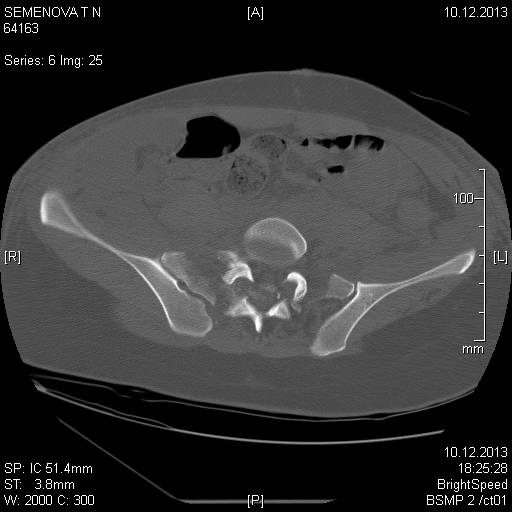

Доброго времени суток коллеги! Прошу вас, подсказать тактику в решении

оперативного лечения следующего сложного повреждения таза. Был ли опыт в

фиксации подобных повреждений?

Травма 03.12.2013,больная переведена из лечебного учреждения соседней

области. На данный момент у больной следующий диагноз: ЗЧМТ,сотрясение

головного мозга;Закр. травма грудной клетки,множественные переломы ребер

справа с повреждением ткани легкого, правосторонний гемопневмоторакс,

состояние после торакоцентеза; Закр.травма живота,разрыв

селезенки,гемоперионеум, состояние после лапаротомиии спленэктомии;

Закр. оскольчатый перелом сред-верх\3 левой бедренной кости, состояние

после накостного металлостеосинтеза; Закр.поперечный переломовывих на

уровне S1S2, многооскольчатый перелом латеральных масс крестца с обеих

сторон,перелом обеих лонных и седалищных костей.

Перелом поперечных отростков L1,L2,L3,L4, L5 позвонка справа. ШОК 3ст.

Вкратце изложил диагноз.

В настоящее время состояние больной тяжелое. Первым этапом планируем

наложить АНФ (переднюю раму) После стабилизации состояния необходимо

будет выполнить фиксацию.

Имеется один вопрос - какие импланты необходимы т.е. в какой комбинации

и какая последовательность фиксации?